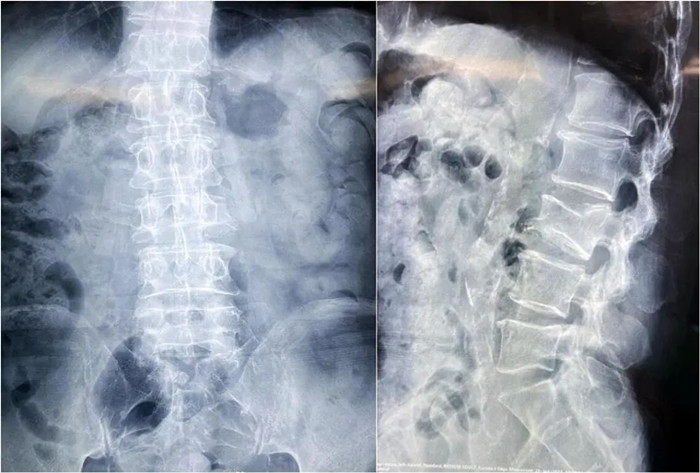

患者情況:腰椎L3壓縮性骨折

南京醫(yī)科大學(xué)第二附屬醫(yī)院骨科副主任醫(yī)師王伯堯帶領(lǐng)團(tuán)隊(duì)成功完成經(jīng)皮椎體球囊擴(kuò)張成形術(shù)(PKP)。該患者為腰椎陳舊性壓縮性骨折,腰部疼痛難忍,活動(dòng)受限,生活受到影響。王醫(yī)生借助普愛(ài)醫(yī)療大平板C臂機(jī)高清的圖像及靈活的擺位,快速定位椎弓根位置,確定進(jìn)針點(diǎn),使得手術(shù)得以更加高效和準(zhǔn)確地完成。

患者術(shù)前影像